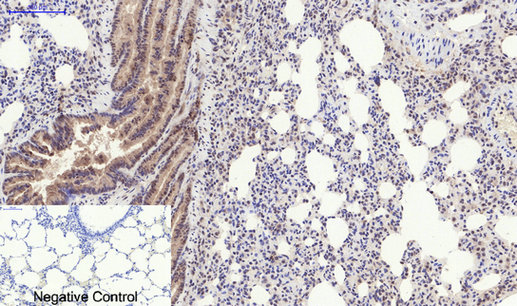

- Immunohistochemistry analysis of paraffin-embedded rat lung tissue using Phospho-PERK (Thr982) antibody.High-pressure and temperature Sodium Citrate pH 6.0 was used for antigen retrieval.